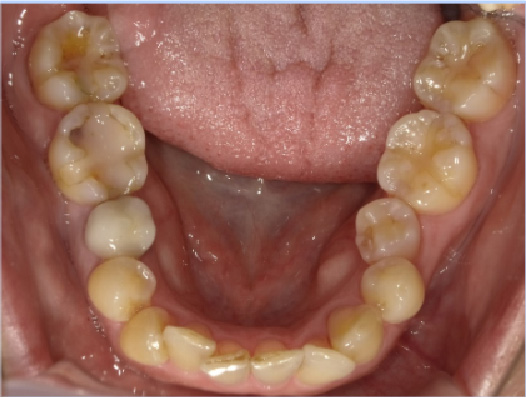

狭い歯列(狭窄歯列)によって、舌が歯列の中に収まらない状態です。

●高口蓋 ●低位舌 ●口呼吸

狭窄歯列(高口蓋)

狭窄歯列(低口蓋)

狭窄歯列(低位舌)

右のように、狭窄歯列だと舌は、狭い歯列に阻まれて、前方や上方の口蓋に自由に動くことができません。その結果、舌は低い位置(低位舌)にあり、前方に出ず後方に位置するので、気道が狭くなってしまっています。

一方、左のように、広い歯列だと舌は、前方にも上方にも自由に動けるので、舌は普段は口蓋についていて鼻呼吸が無理なくできているのです。

狭い歯列(狭窄歯列(きょうさくしれつ))

高口蓋(上顎が深い→鼻腔が狭い)

舌が歯列に納まらない→低位舌

歯並びが悪い

かみ合わせが悪い